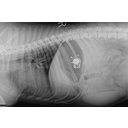

Figure-2-Gastric-foreign-body-lateral-radiograph diagnosis.jpeg